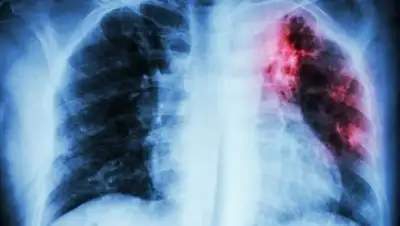

За последние пять лет на рабочем месте туберкулезом заболели 56 врачей, медсестер и санитаров экспертных учреждений.

По его данным, за последние пять лет на рабочем месте туберкулезом заболели 56 врачей, медсестер и санитаров экспертных учреждений, различными формами вирусного гепатита - 26 сотрудников.

«Случаи такого заражения я отмечу только в трех областях: Акмолинской, Карагандинской и Мангистауской. Получается, что от опасного заражения никто не застрахован. При этом при объединении центров судебной медицины и судебной экспертизы судебным медикам были отменены доплаты за работу с трупным материалом и лицами, зараженными ВИЧ СПИД. Вопрос восстановления этих доплат правительством до сих пор не решен», - подчеркнул Н. Абдиров.